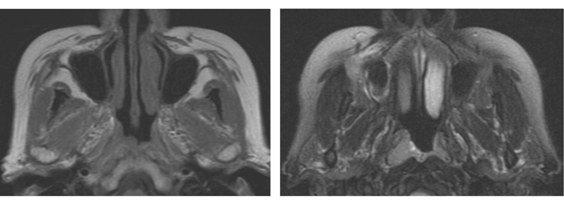

患者,男,53歲,發現鼻塞及右側頸部包塊、面部疼痛一個月余,查體左頸部有一質硬的包塊。MRI如圖所示: